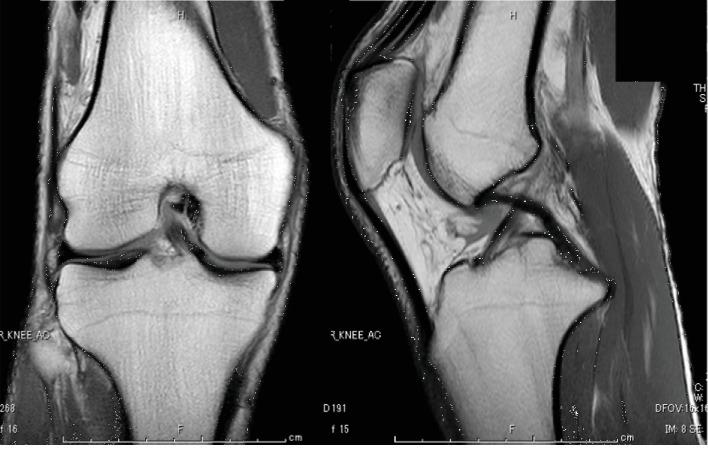

We report the case of painful snapping pes syndrome caused by the gracilis tendon. A 26-year-old man presented with acute right knee pain and restricted extension. Although snapping could not be reproduced due to severe pain, the snapping of the gracilis tendon could be specifically diagnosed using ultrasonography and lidocaine injection. Because of the failure of conservative treatment, surgery was performed. The distal attachment of the gracilis tendon was released, and the symptom disappeared quickly. There was no recurrence at the 10-month follow-up.

摘要

我们报告一例由股薄肌腱引起的疼痛性弹响足综合征病例。一名26岁男性出现右膝急性疼痛和伸展受限。尽管由于剧痛无法重现弹响,但通过超声检查和利多卡因注射可明确诊断为股薄肌腱弹响。由于保守治疗无效,遂行手术。松解了股薄肌腱的远端附着点,症状迅速消失。10个月随访时无复发。